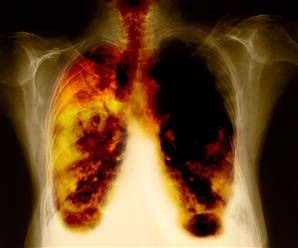

pulmones dañados sintomas, fotos de personas con cáncer del pulmón, pulmones dañados imagenes, RADIOGRAFIA DE PULMON POR CARBON